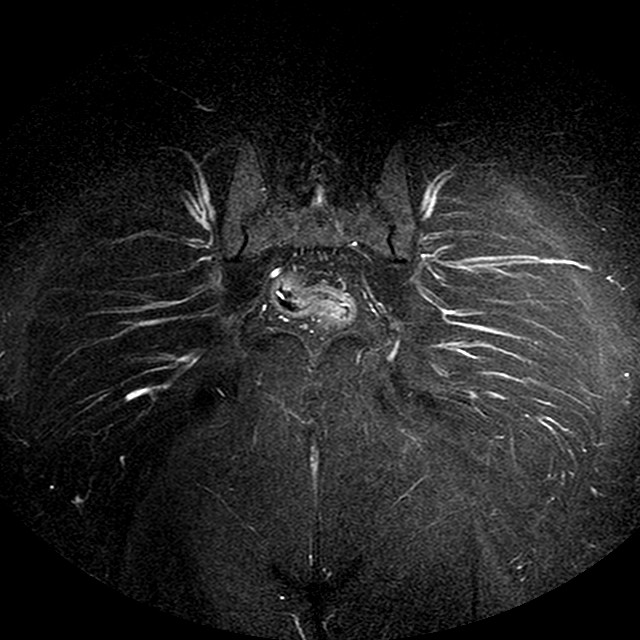

STIR

Evidenti e simmetriche alterazioni osteofitosiche in regione coxo femorale con riduzione delle rime articolari. Degenerazione completa del cercine glenoideo. Non attuali segni di versamento articolare. Non segni di edema osseo che escludono attuale algodistrofia od osteonecrosi. Lieve e simmetrica riduzione del trofismo della muscolatura glutea.